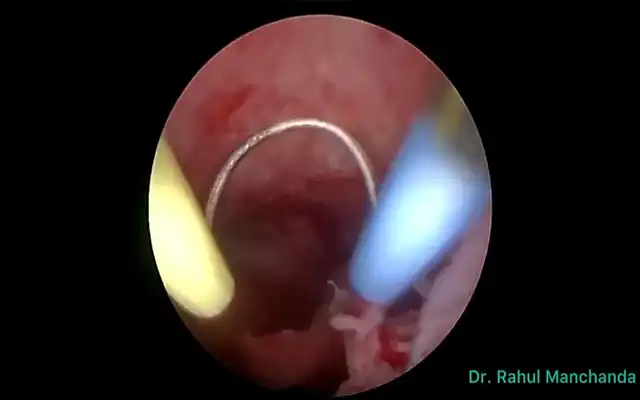

Hope Beyond Adhesions: Stepwise Hysteroscopic Adhesiolysis and Cavity Restoration in Severe Intrauterine Adhesions (Video article)

Hope Beyond Adhesions: Stepwise Hysteroscopic Adhesiolysis and Cavity Restoration in Severe Intrauterine Adhesions (Video article)2025-12-18T13:18:01+00:00